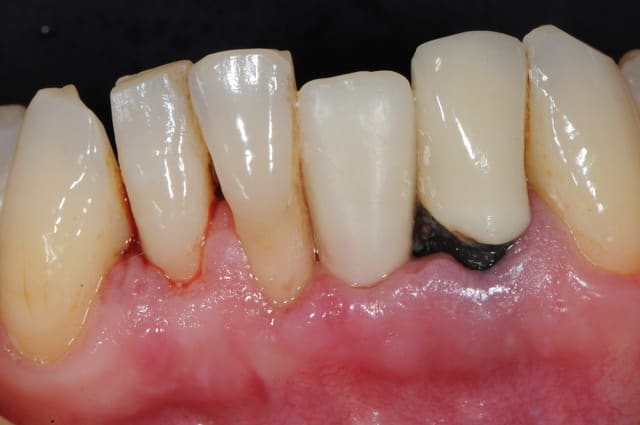

et ici ?? vous feriez quoi ?

32 et 42 pas mobiles

malheureusement, l'espace est réduit pour mettre deux implants.

comment avez vous déjà géré ce type de cas ??

le haut est déjà traité...